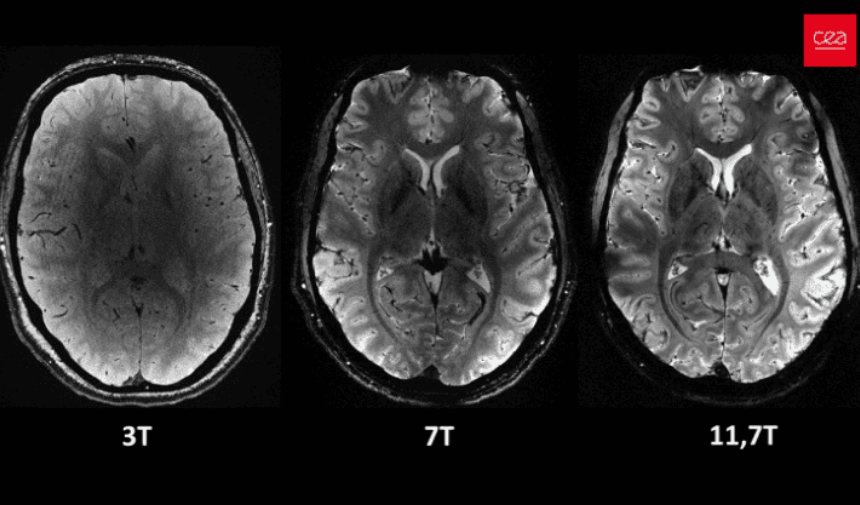

İNSAN BEYNİNİN EN NET GÖRÜNTÜSÜ

Fransa Atom Enerjisi ve Alternatif Enerjiler Kurumu (CEA), insan beyninin dünyanın en güçlü manyetik rezonans görüntüleme (MRI) cihazıyla elde edilen en net görüntüsünü yayımladı. Nisan ayına damga vuran bu gelişme, 20 yıldan uzun süren çalışma sonucu elde edildi. MRI cihazı, son birkaç ayda yaklaşık 20 sağlıklı gönüllü üzerinde test edildi ve neredeyse 4 dakikada beynin en net görüntüsüne ulaşıldı.